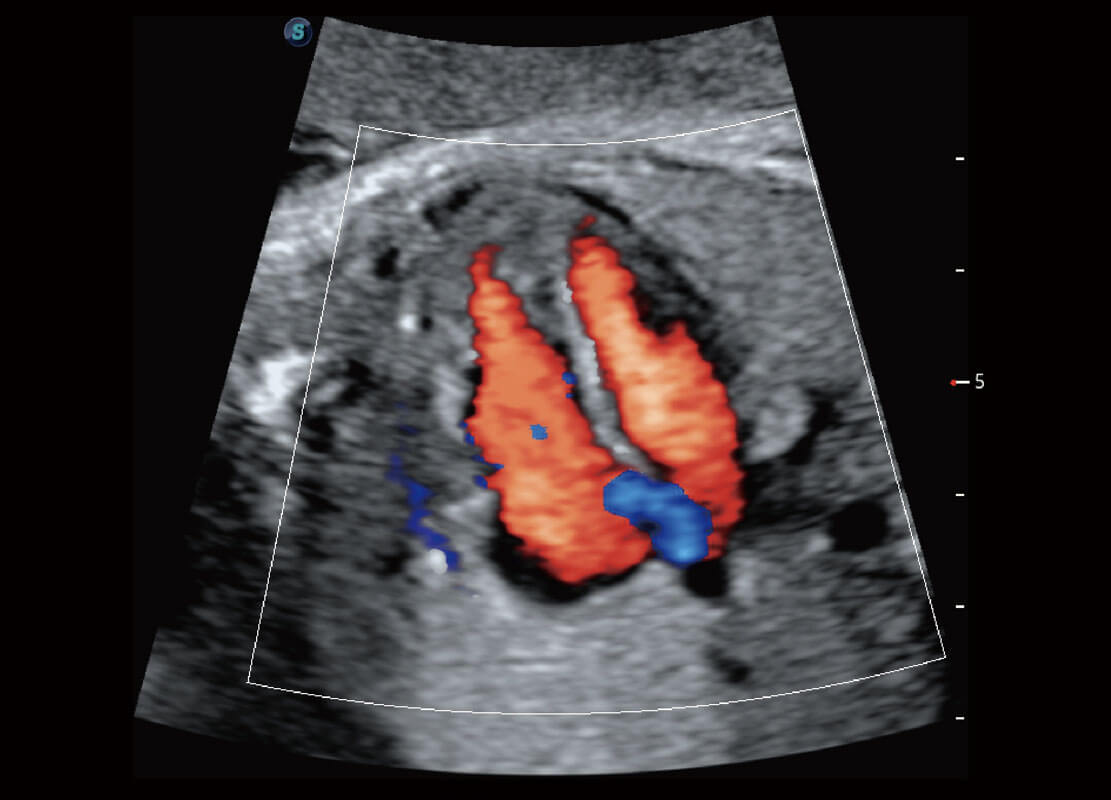

• 四腔心血流

• 右室双出口